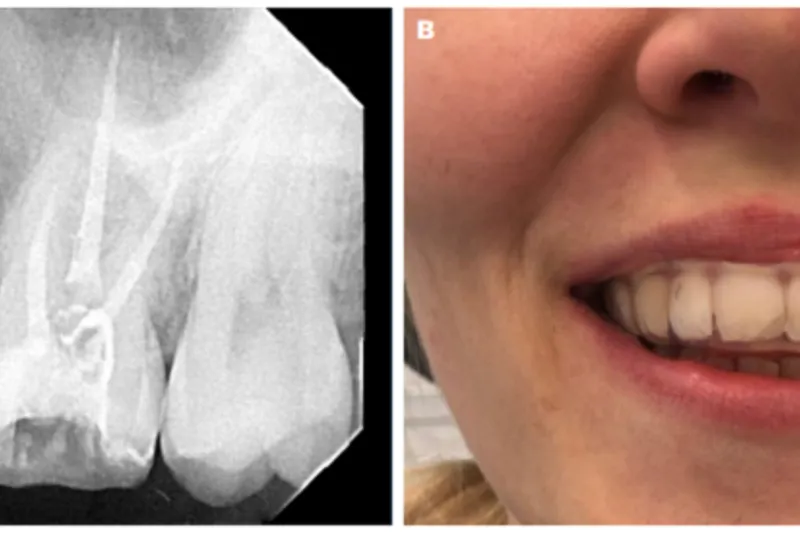

Det vigtigste ved korrekt differentialdiagnostik er muligheden for at undgå forværring af smertetilstande som følge af ikke-indicerede indgreb. International Classification of Orofacial Pain (ICOP) indeholder korte beskrivelser og strukturerede diagnostiske kriterier for orofaciale smerter forårsaget af læsion eller sygdom i de kranielle nerver.

Tandlæger spiller en væsentlig rolle i diagnostik af orofaciale neuropatiske smertetilstande, herunder klassisk trigeminusneuralgi, postherpetisk trigeminal neuralgi samt posttraumatisk trigeminal neuropatisk smerte. Sidstnævnte kan opstå som følge af traumer, men også som følge af almindelige odontologiske procedurer, selvom de er udført lege artis. Det er af afgørende betydning, at patienter med orofaciale neuropatiske smerter får stillet korrekt diagnose og bliver tilbudt relevant behandling, herunder særligt at det undgås at udføre ikke-indicerede invasive indgreb.